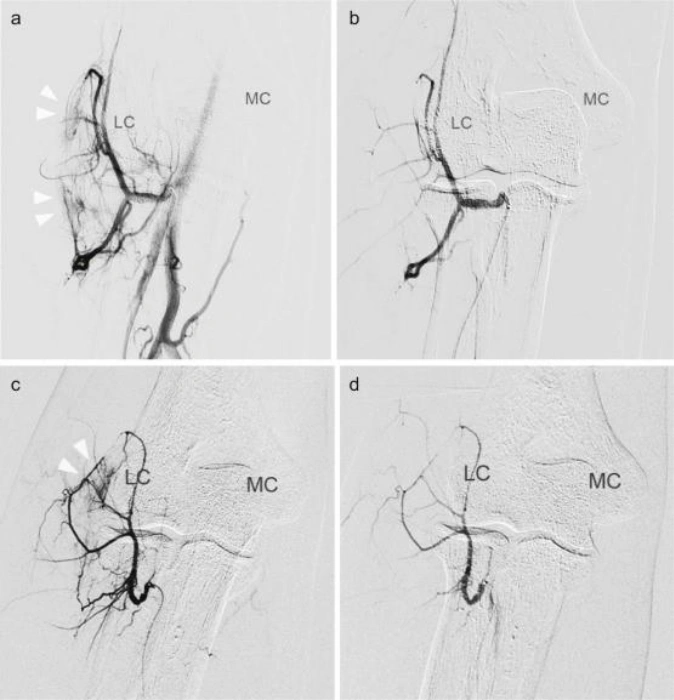

Genicular Artery Embolization (GAE)

An innovative, non-surgical therapy for knee osteoarthritis pain. It works by blocking the tiny inflamed blood vessels in the lining of the knee that contribute to pain and swelling. GAE can significantly reduce knee pain and stiffness, offering relief for patients who want to postpone or avoid knee surgery.